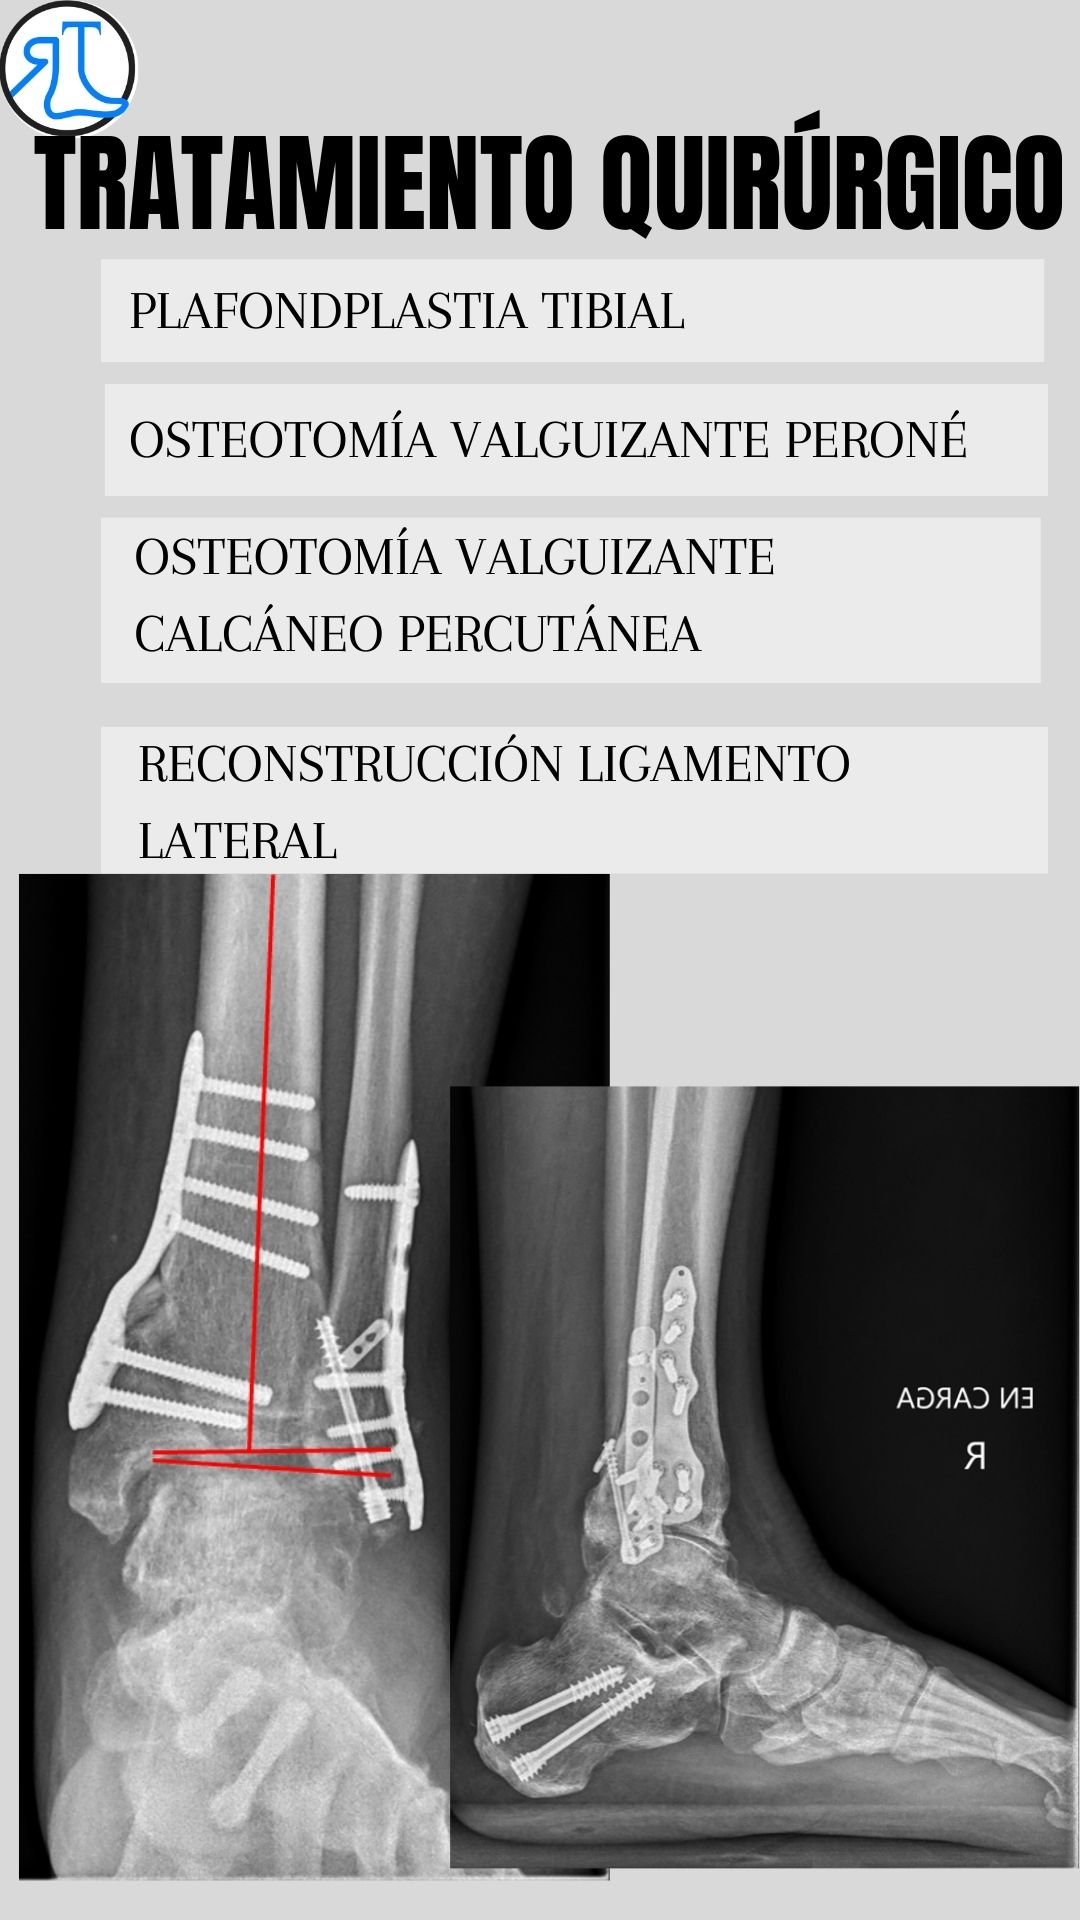

Dada su edad y la existencia de una artrosdesis en el tobillo contralateral decidimos una cirugía de preservación articular mediante plafondplastia de apertura medial. Se asoció osteotomía valguizante de peroné, osteotomía calcánea percutánea valguizante y reconstrucción de ligamento lateral del tobillo mediante aloinjerto como recomiendan las últimas publicaciones en la literatura en casos similares.

Como podéis ver en las imágenes se consiguió mejorar el eje del talón trasladando el eje de carga de al extremidad hacia la zona del tobillo más sana. A pesar de no corregir del todo el tilt talar el paciente se encuentra asintomático.